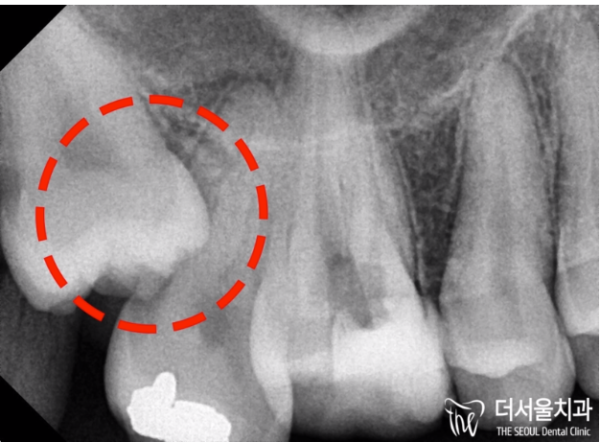

모란역치과 더서울치과에서 파노라마 엑스레이 촬영을 통해

치아 내부를 확인했습니다. 내부에 검은색으로 변한것이 확인됩니다.

충치가 생겼다는 의미인데요.

Through a panoramic X-ray at Moran Station Dental Clinic The Seoul Dental Clinic

I checked the inside of the tooth. It is confirmed that the inside turned black.

It means I have a cavity.